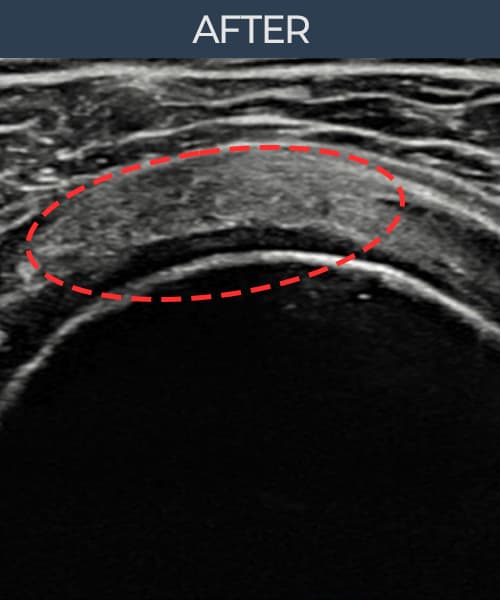

시술 전 초음파 측정 결과 파열 크기는 11mm × 6mm (힘줄 두께의 약 58% 결손)로 확인되었습니다. 시술 전 초음파에서 회전근개의 연속성 단절과 부착부 인대 두께의 현저한 감소가 확인되었습니다. 시술 후 초음파에서는 봉합된 인대의 연속성이 회복되고 부착부 두께가 정상 범위로 증가하였으며, 내부 에코 패턴도 균질하게 개선되었습니다.

50대 초반 남성 환자분으로, 물류 창고에서 무거운 물건을 반복적으로 들어올리는 작업을 10년 이상 해오신 분이었습니다. 타 기관에서 충격파 치료를 3개월 받았으나 효과가 없어 내원하셨고, 정밀 초음파 검사에서 회전근개 부분파열과 인대 손상이 복합적으로 확인되었습니다. 단순 주사 치료나 물리치료로는 구조적 문제를 해결하기 어렵다고 판단하여 초음파 유도 하 축소봉합술을 시행하였습니다. 시술 당일 귀가 후 보조기를 착용하였으며, 4주 후부터 단계적 재활 운동을 시작하였습니다. 시술 후 6주 시점에 초음파 재검사에서 봉합 상태가 양호함을 확인하였고, 18개월 최종 경과 관찰에서 인대 두께 회복과 구조적 안정화가 확인되어 직장 복귀에 성공하셨습니다.